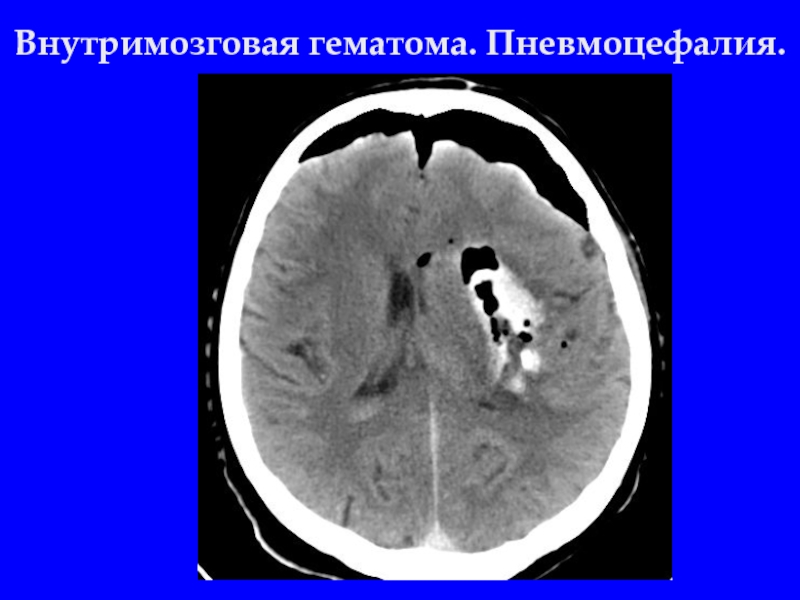

Слайд 25Внутримозговая гематома. Пневмоцефалия.